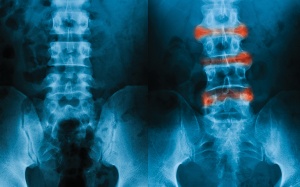

Viêm cột sống dính khớp nếu không được phát hiện và điều trị kịp thời có thể tiến triển nặng, dẫn đến dính khớp và biến dạng khớp. Thông tin trong video dưới đây sẽ giúp bạn...